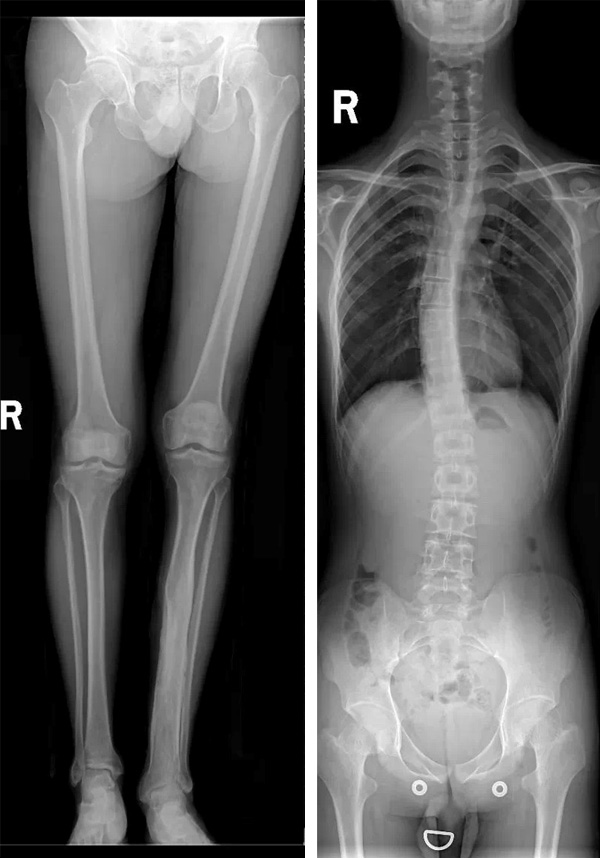

近日,玉溪市中醫(yī)醫(yī)院放射科島津C200第五代動(dòng)態(tài)大平板透視攝影系統(tǒng)投入使用,該設(shè)備可開展全脊柱、雙下肢全長檢查。高清攝影、快速診斷、及時(shí)治療,實(shí)現(xiàn)了全脊柱、雙下肢全長檢查的“無縫拼接”,是脊柱側(cè)彎和下肢畸形等骨科疾病術(shù)前術(shù)后X線檢查的首選方法。

放射科主任吉德磊介紹:“以前拍片子需要好長時(shí)間,需多次擺位。由于平板探測(cè)器最大規(guī)格一般只有43cm左右,而脊柱和下肢全長一般超過了這個(gè)長度,現(xiàn)采用新系統(tǒng)實(shí)現(xiàn)全脊柱及雙下肢全長X線攝片,能直觀的顯示全脊柱、雙下肢全長的整體形態(tài),在一張照片上可獲得較清晰、完整的全景圖像顯示,并可進(jìn)行相關(guān)長度測(cè)量、角度測(cè)量等應(yīng)用。”

市中醫(yī)醫(yī)院放射科這臺(tái)高端懸吊DR具有千萬級(jí)像素,利用其特有的“無縫拼接”技術(shù),可獲得一幅完整的全脊柱和全下肢影像,為臨床在脊柱側(cè)彎畸形和下肢骨關(guān)節(jié)病變?cè)\斷、治療方案制定及術(shù)后復(fù)查提供精準(zhǔn)的測(cè)量。

依據(jù):診斷迅速,及時(shí)治療

近年來,骨科類疾病發(fā)病率逐年遞增,多發(fā)于脊柱側(cè)彎畸形、骨性關(guān)節(jié)炎、風(fēng)濕性關(guān)節(jié)炎、雙下肢畸形,如:關(guān)節(jié)內(nèi)外翻,X、O型腿等常見病癥,常累及下肢髖、膝、踝等負(fù)重關(guān)節(jié),影響生活質(zhì)量,嚴(yán)重時(shí)還會(huì)喪失工作能力。

1、判斷下肢力線,主要用于膝關(guān)節(jié)內(nèi)外翻畸形的測(cè)量,能比較準(zhǔn)確地反應(yīng)骨結(jié)構(gòu)異常和軟組織不平衡對(duì)膝關(guān)節(jié)內(nèi)外翻的最終影響。對(duì)膝關(guān)節(jié)置換的X線評(píng)估尤為重要。

01、可以精確測(cè)量雙下肢的長度;

02、可以更好地判斷下肢力線和解剖學(xué)角度;